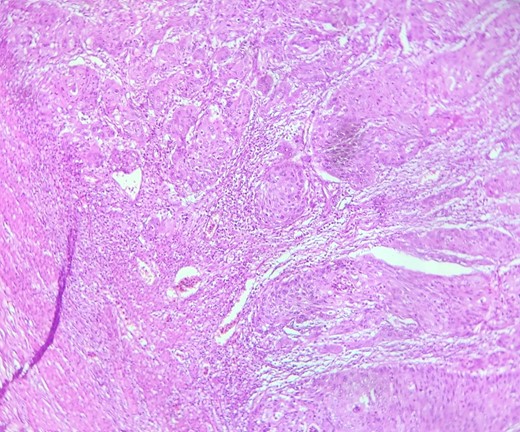

Mr. B. is a 59-year-old patient with no notable pathological history, presenting with melenas associated with marked weight loss. A fibroscopy revealed a thickened and ulcerated gastric mucosa. Abdominal and pelvic CT scans revealed a tissue process in the body and tail of the pancreas invading the splenic hilum, adjacent vessels ans gastric wall, measuring 11 cm long (Fig. 5). A caudal spleno-pancreatectomy enlarged to the colon, omentum and stomach was performed. Macroscopically, the tumor had a grayish–white appearance, poorly limited and indurated on palpation. Histologically, it was a well-differentiated, keratinizing squamous cell carcinoma of the tail of the pancreas (Figs 6 and 7), infiltrating the splenic hilum, gastric wall and colon.

HE section showing nests and sheets of polygonal cells surrounded by fibrotic desmoplastic stroma (x100).